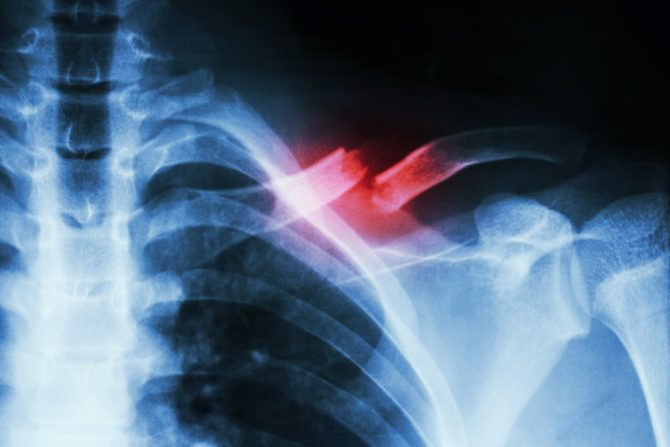

Među ženama u postmenopauzi početni prelom ruke ili zgloba, nadlaktice ili ramena, natkolenice, kolena, potkolenice ili skočnog zgloba i kuka ili karlice, povezani su sa oko 3 do 6 puta većim rizikom za naknadne lomove

Istraživački tim ispitivao je zdravstvenu evidenciju od 1993. do 2018. za više od 157.000 žena, starosti od 50 do 79 godina. Podaci su dobijeni iz Inicijative za žensko zdravlje, nacionalne studije koju je finansirao Nacionalni institut za srce, pluća i krv. Otkrili su da su među ženama u postmenopauzi početni prelom donje ruke ili zgloba, nadlaktice ili ramena, natkolenice, kolena, potkolenice ili skočnog zgloba i kuka ili karlice, povezani sa približno 3 do 6 puta većim rizikom za naknadne lomove. Autori su primetili neka ograničenja u studiji, uključujući činjenicu da su učesnici sami prijavili prelome. Međutim, ranija istraživanja su pokazala da su statistički podaci o prelomima koji su sami prijavljeni prilično tačni, u poređenju sa statistikama iz medicinske evidencije.